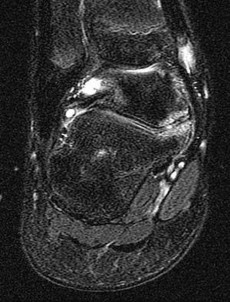

Figures 1a through 1c

Calcaneonavicular (CN) coalition

- Calcaneonavicular (CN) coalition**_

Tarsal coalitions occur when primitive mesenchymal cells fail to differentiate and form the

normal articular separations between the tarsal bones of the hindfoot. Overall incidence is difficult to determine because many affected people are minimally symptomatic or asymptomatic. Symptomatic tarsal coalitions typically present in adolescents as a painful flatfoot; however, there are a number of possible presentations, and occasionally symptoms do not appear until adulthood. Most tarsal coalitions are between the calcaneus and the navicular (CN) and the talus and the calcaneus (TC). Although most TC coalitions are across the middle facet, posterior facet coalitions do occur. Plain radiographic evaluation of suspected tarsal coalition is the mainstay for diagnosis. However, coalitions can be bony or fibrous, and making the diagnosis can be difficult. The addition of CT images to distinguish bony definition and MR images to decipher soft tissue can aid in diagnostics. Bony coalitions appear as definite bony bridging between the bones, while fibrous coalitions are suspected when distortion of the bony anatomy is seen. Bony coalitions are best seen on the oblique view (CN) and Harris axial view (TC). There are a number of secondary signs such as the anteater (AE) sign (elongation of the anterior process of the calcaneus as it extends to the navicular as seen on the lateral view [CN]). talar beaking (traction spur of the talar neck thought to result from abnormal stresses as seen on the lateral view [both CN and TN]), and the “C” sign (a continuous cortical contour from the medial talus to the sustentaculum tali [ST]) as seen on the lateral view (TC). A number of newer signs are not as well known, such as a broad mediolateral dimension of the navicular on the anteroposterior (AP) view (the

navicular is wider than the talar head [CN]), nonvisualization of the middle facet on the lateral view (TC), the brick sign (a normal ST is flat, but a distorted ST is enlarged and curved [CN]), and a tapered lateral navicular bone as seen on the AP view (the medial navicular [CN] is much thicker than the lateral navicular).

Figure 1a shows talar beaking (TB), an AE, and an open middle facet (MF). Figure 1b shows a wide navicular (WN), and Figure 1c shows an abnormal articulation between the calcaneus and the navicular, all consistent with a CN coalition.